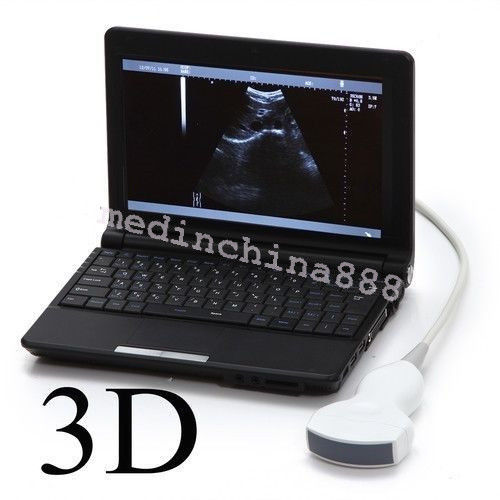

Laptop LCD Digital 10.1-Inch Ultrasound Scanner Overview

monitor: 10.1â high-resolution TFT LCD

The Laptop LCD Digital 10.1-Inch Ultrasound Scanner is designed for high-quality imaging. This portable device offers detailed visuals, allowing healthcare professionals to deliver accurate diagnoses effortlessly. Equipped with both convex and transvaginal probes, it enhances versatility in various medical procedures. Its compact design ensures that you can carry it easily between locations, making it an essential tool for any medical practice. The user-friendly interface further simplifies operation, so you can focus on patient care without unnecessary distractions.

Enhanced User Experience

This ultrasound scanner is not only portable but also built for convenience. The 10.1-inch LCD screen displays clear images, which means you can view results in real-time without any lag. It provides essential features like freeze and rewind functions, enabling you to review images quickly. Additionally, because it connects easily to printers or USB devices, you can generate hard copies of your findings without any hassle. So, whether in a clinic or at a patient's home, this laptop ultrasound scanner adapts to your needs.